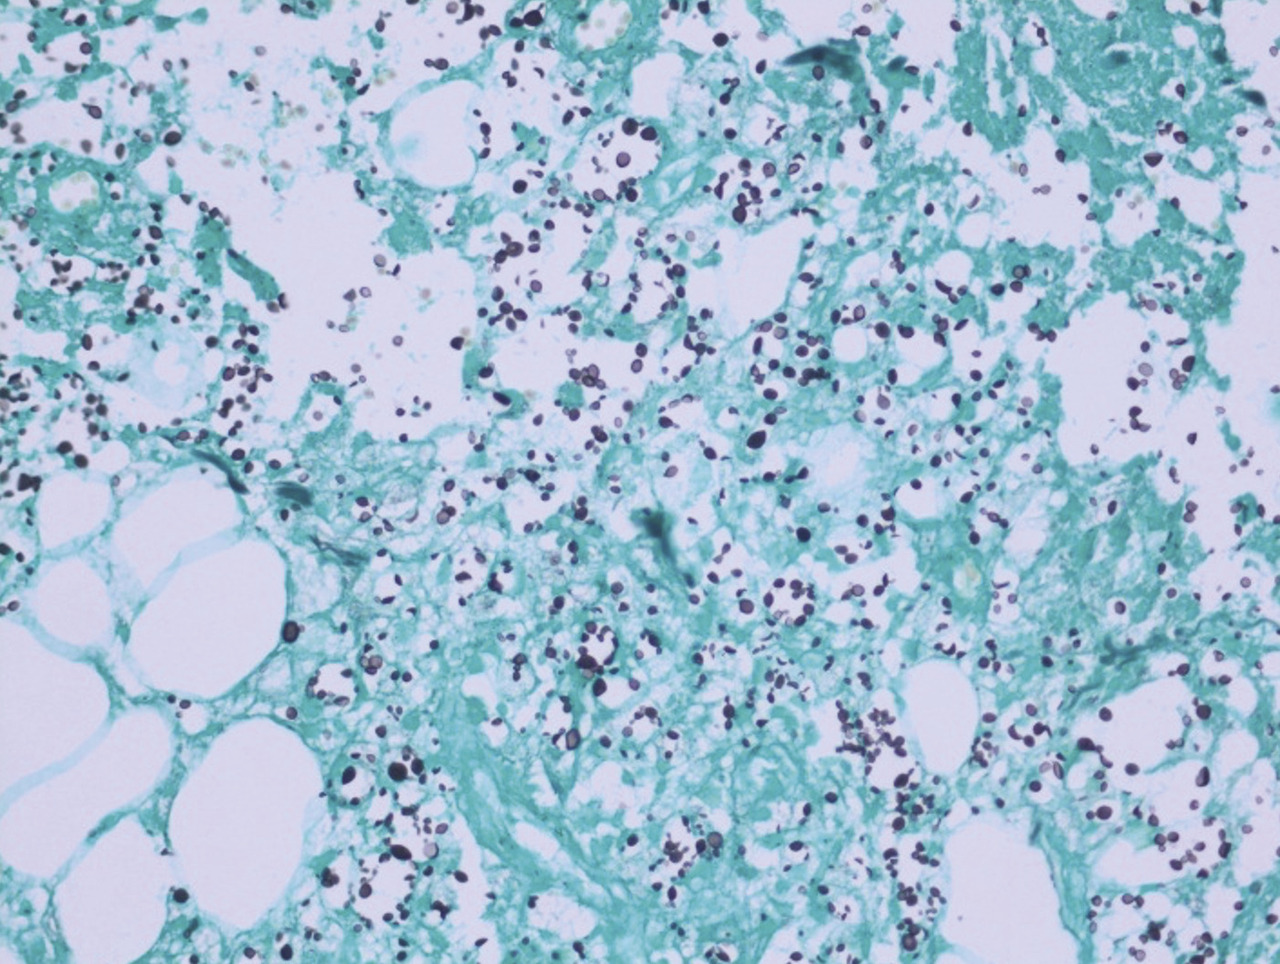

Après quelques jours de traitement immunosuppresseur, une douleur intense et insomniante s’installe, avec érythème et tuméfaction du membre supérieur gauche. Les examens complémentaires retrouvent une protéine C-réactive (CRP) à 300 mg/L, des hémocultures stériles, une échographie Doppler artérioveineuse sans thrombose. Le diagnostic d’une dermohypodermite bactérienne non nécrosante est évoqué dans un premier temps. La patiente est alors traitée par antibiothérapie (amoxicilline et acide clavulanique). L’évolution est défavorable, avec apparition de lésions nécrotico-hémorragiques rapidement extensives (fig. 2 ). Une imagerie par résonance magnétique (IRM) [fig. 3 ] montre une infiltration des parties molles sous-cutanées, des loges musculaires associées à des bulles d’air, en faveur d’une fasciite nécrosante. Une exploration chirurgicale permet de réaliser des biopsies profondes au niveau du fascia et du muscle. Le résultat histologique, après coloration de Grocott, montre une cryptococcose avec multiples foyers de nécrose de liquéfaction (fig. 4 ). Le diagnostic de fasciite nécrosante cryptococcique est finalement retenu. La recherche de l’antigène sérique cryptococique est positive (1 : 2 000, test d’agglutination au latex). La sérologie VIH (virus de l’immunodéficience humaine) est négative. À défaut d’amphotéricine B, du fluconazole à la dose de 400 mg/j est administré. L’évolution a été défavorable, avec décès à la suite d’un choc septique.

Après quelques jours de traitement immunosuppresseur, une douleur intense et insomniante s’installe, avec érythème et tuméfaction du membre supérieur gauche. Les examens complémentaires retrouvent une protéine C-réactive (CRP) à 300 mg/L, des hémocultures stériles, une échographie Doppler artérioveineuse sans thrombose. Le diagnostic d’une dermohypodermite bactérienne non nécrosante est évoqué dans un premier temps. La patiente est alors traitée par antibiothérapie (amoxicilline et acide clavulanique). L’évolution est défavorable, avec apparition de lésions nécrotico-hémorragiques rapidement extensives (